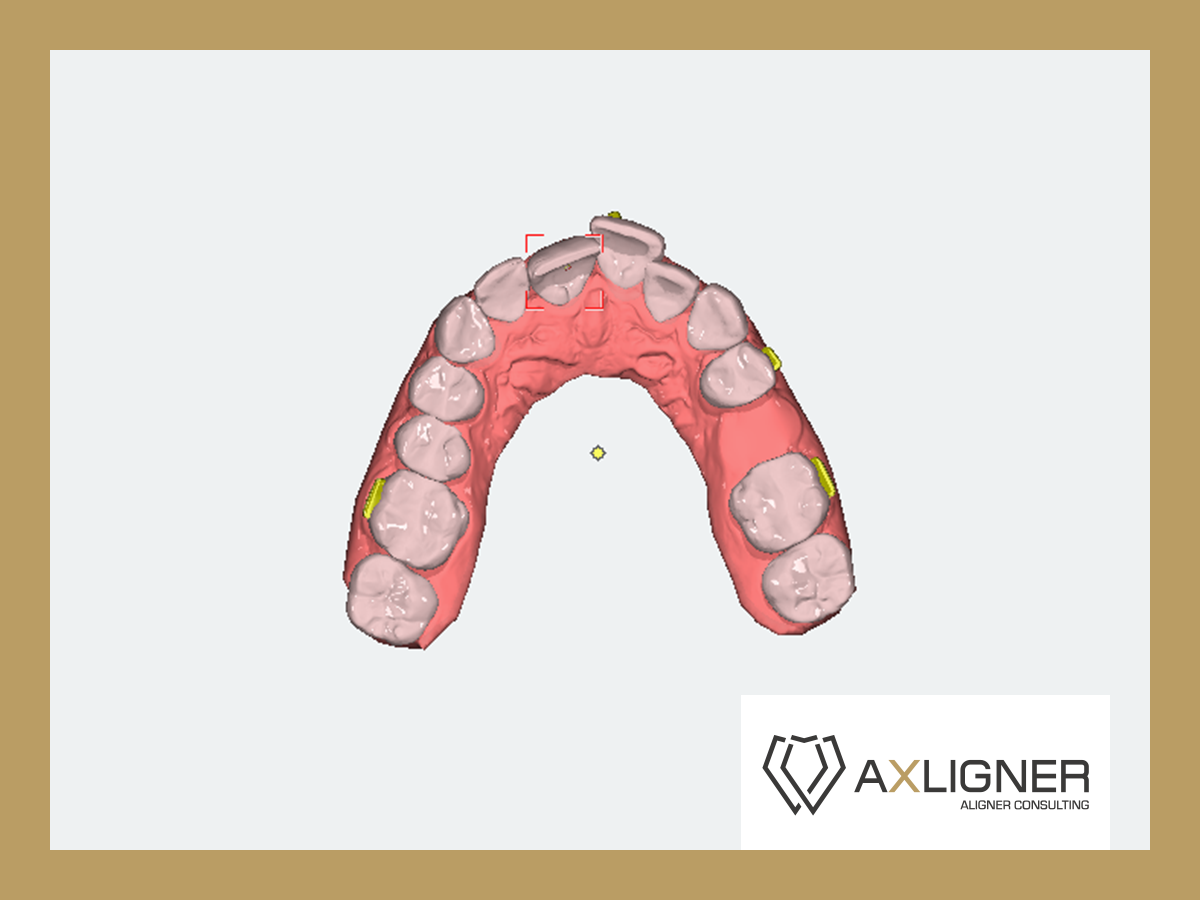

Analizę przemieszczeń zębów w zakresie mezjalizacji trzonowców w szczęce oraz przemieszczenie przedtrzonowca górnego rozpoczęto dopiero po uzupełnieniu zlecenia o analizę zdjęcia panoramicznego oraz badań dodatkowych. Opisano trzy opcje leczenia tego pacjenta. Pierwsza propozycja obejmowała brak mezjalizacji d. 26 i d.27; dystalizację w zakresie wybranych zębów. Druga propozycja obejmowała minimalną dystalizację drugiej ćwiartki łuku zębowego. Trzecia propozycja obejmowała sekwencyjną mezjalizację d. 26 oraz d. 27.

Cyfrowy plan leczenia przeanalizowano pod kątem osiągnięcia klinicznego celu zaplanowanego przez lekarza. Zaplanowana na cyfrowym planie leczenia mezjalizacja nie uwzględniała rekomendowanego sekwencyjnego przemieszczania zębów. Oznaczało to bardzo mało prawdopodobne zajście tych ruchów w jamie ustnej u pacjenta. Opisano lekarzowi, na czym polega sekwencyjna mezjalizacja zębów i jak zaprojektować ją w nowym planie leczenia. Zwrócono uwagę, że tego typu przemieszczenia zębów są bardzo wymagające, dlatego lekarze do zwiększenia możliwości ich zajścia stosują np. miniimplanty ortodontyczne. Opisano wpływ ilości i jakości attachmentów na zwiększenie przewidywalności ruchów zębowych.

- Zmodyfikować sekwencje mezjalizacji trzonowców.

- Plany leczenia dzielić na części, w których przemieszczane są pojedyncze zęby, a nie wszystkie zęby w maksymalnych zakresach jednocześnie.

- Wyjaśniono wpływ attachmentów na zwiększenie przewidywalności ruchów zębowych.